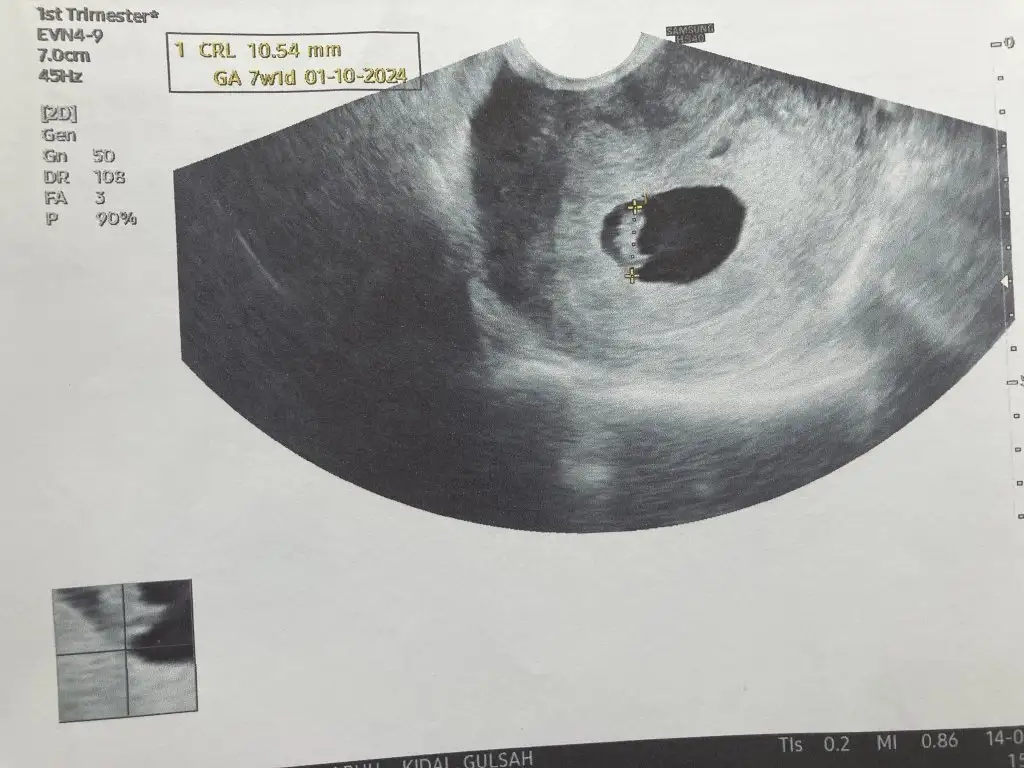

Maşallah ben 7+6Valla hiç bilmiyorum bende herkes yazsın kızlar kaç günlüksünüz ben 10+2